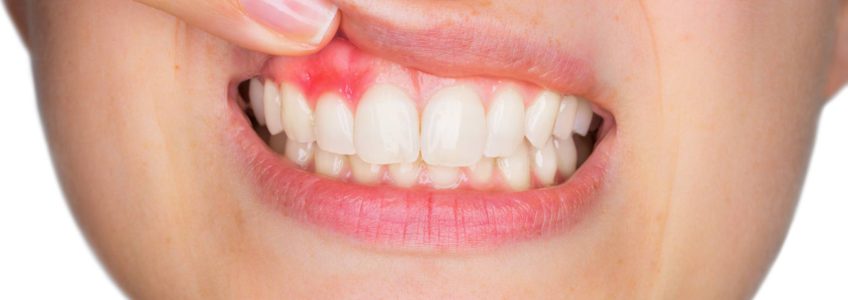

IMPORTANCIA DE LA GINGIVITIS

De la periodontitis, periodontosis, de la dentición difícil, de la formación de bolsas en encía, de la osteitis, etc., en el marco de un suceso focal dentógeno. Al respecto hay que decir lo siguiente:

La efectividad focal de estos cuadros clìnicos se basa primero en los mismos procesos inflamatorios crònicos y segundo en la reaccionabilidad vegetativa de la gigiva. Esta última "ratio" no se conocìa hasta el momento y sòlo ha podido ser aclarada gracias a las ùltimas investigaciones histològicas, electrónico-microscópicas e histo-químicas hechas por PLENK junior y RAAB (1969 1970) en nervios de la gingiva humana. Hemos comprobado allì por primera vez en la historia de la odontología científica la existencia de nervios adrenergos y autónomos (en la encia) lo que permite entender correlaciones funcionales de la misma con todo el organismo y a las que les faltaba el substrato morfològico.

La importancia clínica de este hallazgo se publicó por primera vez en 1970 (RAAB). La comprobación de que sí existen nervios vegetativos en la gingica es apropiada para explicar la hasta ahora oscurísima patofisiología de efectos a distancia "lanzados desde la gingiva" hacia todo el organismo y viceversa daños que le vienen a la gingiva proveniente de la mas variada y general gama de insultos patológicos de tipo tanto físico como psíquico (RAAB 1961). En la Universidad tenemos ya apabullantes estadísticas que le sirven de ejemplo a todo lo que estamos exponiendo.

El internista alemán M.L.Veil (1939) describió que en la mayoría de los casos con periodontosis las amigdalas se hallaban afectadas, o viceversa que una periodontosis severa y fétida solo lograba curarse después de una amigdalectomía. Se sabe además de casos en que existe una gingivitis crónica o aguda, pueden aparecer simultáneamente afecciones de caracter reumático en varias articulaciones, o molestias a distancia circunscritas a órganos. Este caso se da preferentemente en aquellos lugares del cuerpo cuya estructura heredada presenta constitucionalmente una clara debilidad de su sistema o también alrededor de sitios que sufrieron enfermedades años atrás. Sucede lo mismo con áreas cuya sobrecarga tisular es evidente por ejemplo: allí donde la estática del esqueleto está alterada. Todos estos factores crean en el cuerpo puntos de resistencia menor, mejor dicho puntos de reacción mayor, de tal modo que es allí donde anidan en primera linea irritaciones e interferencias.

Hasta ahora se venía culpando de todos estos sucesos focales que siempre acompañan, así como también a las alteraciones osteíticas. Sabemos que bajo la influencia de una situación hormonal de stress permanente como la pubertad, el climaterio y el embarazo o también un schock psíquico, como por ej: situaciones conflictivas en el trabajo y en la familia, puede presentarse una gingivitis sin que para ello podamos encontrar la culpabilidad de algún factor local. Las interpretaciones dadas a estos hechos reales no lograron satisfacernos núnca. Según nuestros conocimientos actuales sobre la morfología de la gingiva humana salta a la vista la explicación siguiente: La existencia de fibras vegetativas nerviosas de tipo adrenergico y autónomo en la encía humana, cosa hasta ahora desconocida, comprueba sin lugar a dudas que toda la estructura de sostenimiento y soporte del diente junto a su tejido conectivo elástico que le garantiza su función orgánica de cohexión y fortaleza, se somete a las regulaciones vegetativas de todo el organismo, a través de la interconexión que les facilita el tejido conectivo blando, rico en células y entretejido en toda la estructura elastica en unión con las citadas fibras nerviosas vegetativas y autónomas.

Este hecho le da capacidad para reaccionar y regular vegetativamente en forma indipendiente. En este reconocimiento fundamental está la importancia clínica de los resultados de nuestras investigaciones científicas. A esta circunstancia se debe también el que nosotros, a nivel academico, hayamos podido comprender y luego aceptar la patofisiología y la patogenesia de efectos a distancia desencadenados desde terrenos periodontales y asímismo las diversas patologías presentadas por la gingiva como provenientes de toda suerte de influencias externas e internas. Nuestras múltiples observaciones clínicas recibieron en base a los resultados de nuestras investigaciones científicas, por primera vez, la correspondiente corroboración morfológica.